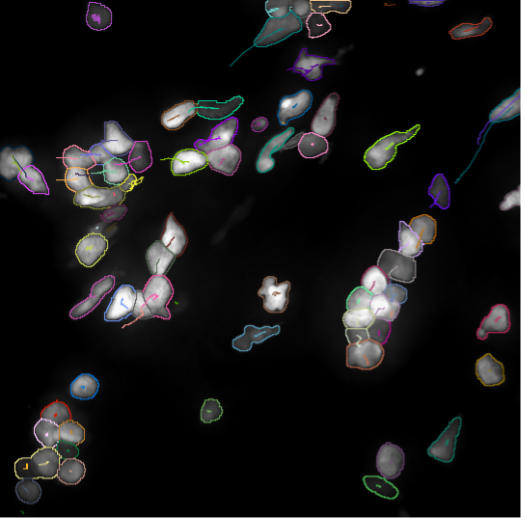

Imaging Platform

The central imaging core facility at the MPI for heart and lung research, provides a wide range of services and trainings, project specific support and full services for more than 100 scientists at the institute as well as for their collaboration partners. We also offer training for image analysis, develop custom analysis pipelines and help with data storage and archiving.